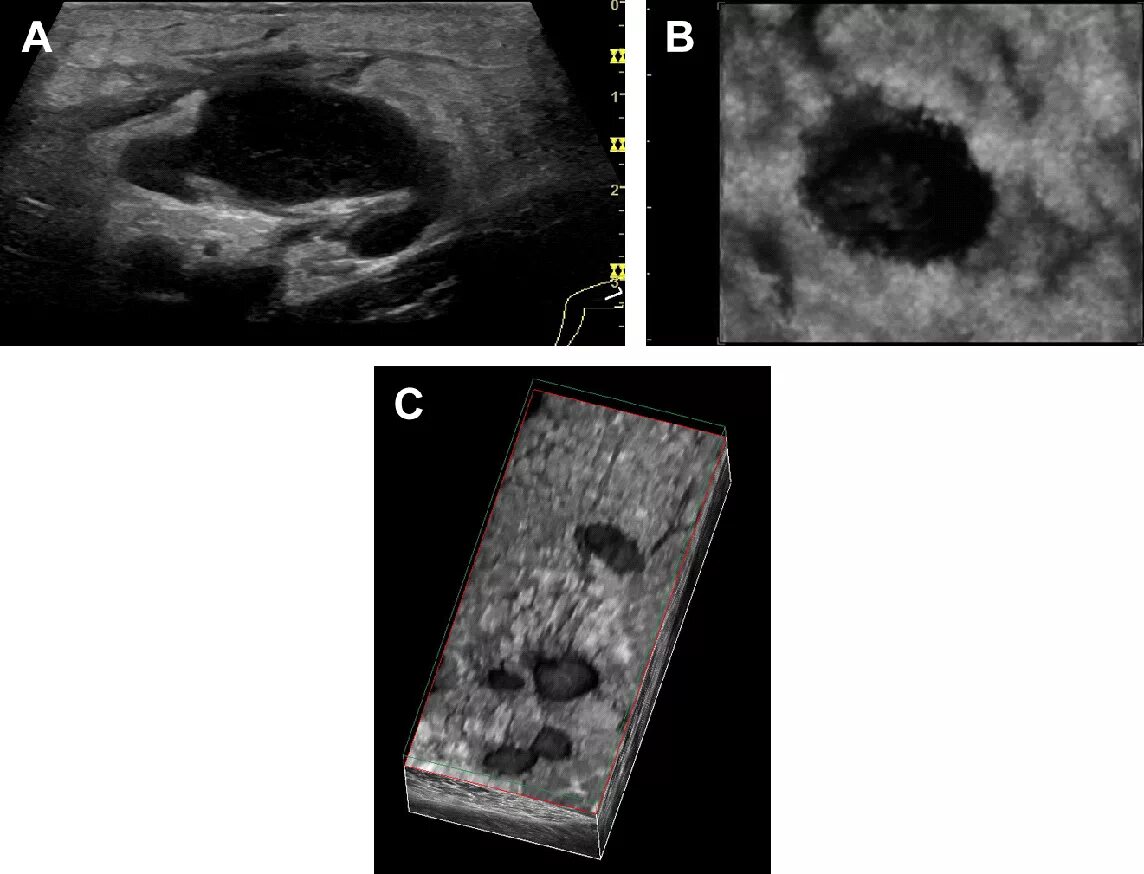

Метастазы в лимфоузлах прогноз жизни